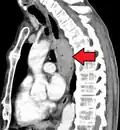

Although an occlusive tumor may be suspected on a barium swallow or barium meal, the diagnosis is best made with an examination using an endoscope. This involves the passing of a flexible tube with a light and camera down the esophagus and examining the wall, and is called an esophagogastroduodenoscopy. Biopsies taken of suspicious lesions are then examined histologically for signs of malignancy.

Additional testing is needed to assess how much the cancer has spread (see § Staging, below). Computed tomography (CT) of the chest, abdomen and pelvis can evaluate whether the cancer has spread to adjacent tissues or distant organs (especially liver and lymph nodes). The sensitivity of a CT scan is limited by its ability to detect masses (e.g. enlarged lymph nodes or involved organs) generally larger than 1 cm.[44][45] Positron emission tomography is also used to estimate the extent of the disease and is regarded as more precise than CT alone.[46] PET/MR as a novel modality has shown promising results in preoperative staging with fair feasibility and good correlation in comparison to PET/CT. It can enhance tissue differentiation with lowering the radiation dose to the patient.[47] Esophageal endoscopic ultrasound can provide staging information regarding the level of tumor invasion, and possible spread to regional lymph nodes.

Contrast CT scan showing an esophageal tumor (axial view)

Contrast CT scan showing an esophageal tumor (coronal view)